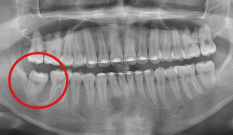

자료 채득

X-ray, 구강 내ㆍ외 카메라 사진, 치아 모형, 턱관절 및 치주 상태,